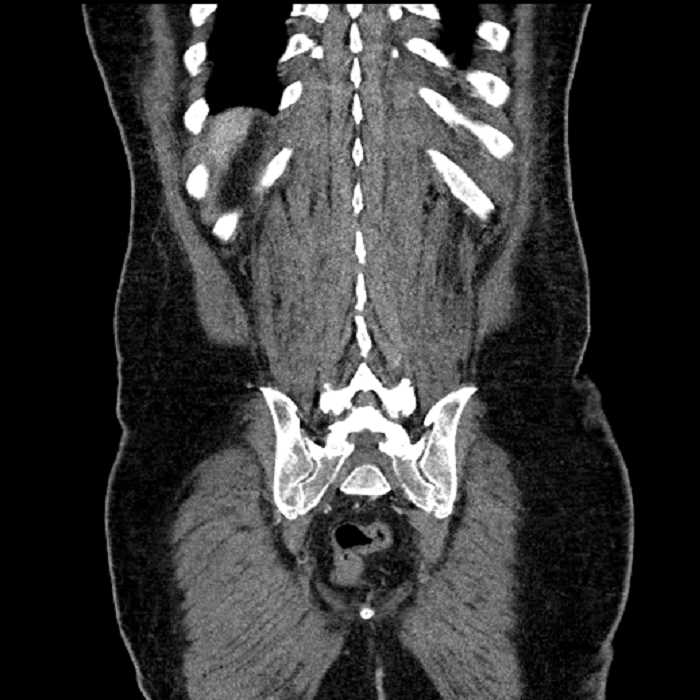

Age: 63

Sex: Male

Indication: Abdominal pain

Findings

• Lower chest

• Mild cardiomegaly

• Mild dependent atelectasis

• Abdomen/Pelvis

• MSK

• No acute findings

• Ankylosis of both sacroiliac joints

• Circumscribed sclerotic lesion in the left anterolateral seventh rib without aggressive features, likely a bone island